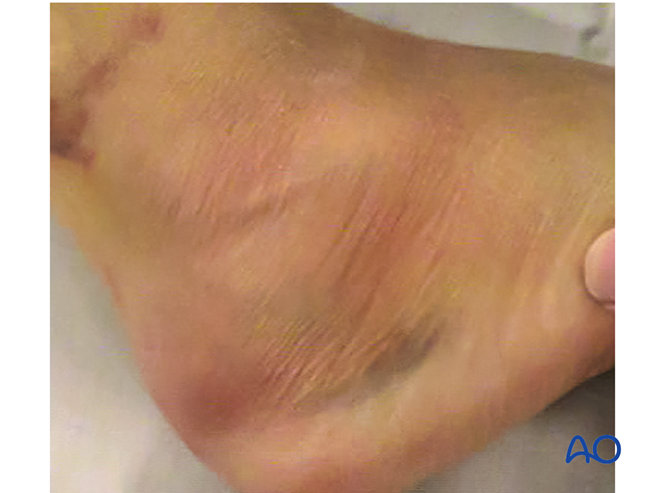

足外侧皮肤皱纹恢复可作为手术时机的参考。通常经皮距下关节手术的最佳时间为伤后2-5天。延迟过久可能导致复位困难及切口闭合问题。

图示为伤后14天符合手术条件的足部,可见“皱纹征”。